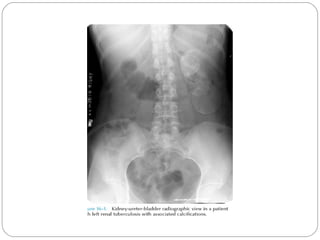

GU Tb-plain KUB

Disparity in renal size on plain films may indicate

early increase in size of the affected kidney due to

caseous lesions or a shrunken fibrotic kidney of

autonephrectomy.

Calcifications are seen in 30% to 50%

A characteristic diffuse, uniform,extensive

parenchymal, putty-like calcification, forming a lobar

cast of the kidney is seen with autonephrectomy

Calculi may also be seen in the collecting system or

ureter secondary to stricture formation.

 Ureteral calcifications are rare and are

characteristically intraluminal as opposed to the mural

. Bladder wall calcifications seen in late cases of

bladder contraction.

 Calcifications of the prostate and seminal vesicles are

seen in 10% of cases .

Plain film findings suggestive of tuberculosis may be

seen in surrounding tissues such as erosions of the

vertebral bodies or calcifications in a cold abscess of

the psoas muscle.